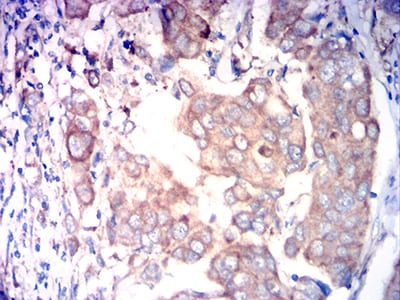

分类: 科研抗体货号: 31766别名: FAPA; SIMP; DPPIV; FAPalpha应用: IHC,FCM反应种属: Human